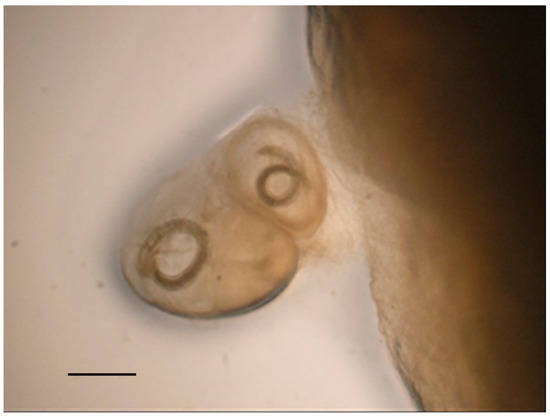

| Barn owl 1 | Intestine | Sarcocystis dispersa (Apicomplexa: Sarcocystidae) | ||||